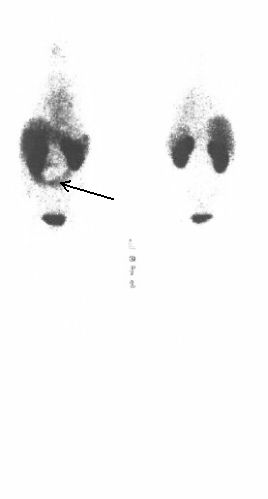

CEA-Scan: celotělové zobrazení (5 hod.po aplikaci)   CEA-Scan: celotělové zobrazení 24 hod. po aplikaci)

/ Obrázek č. 1: celotělové vyšetření v AP a PA

projekci 5 hod po aplikaci

/ Obrázek č. 2: 24 hod po aplikaci v AP a PA

projekci /

Provedena celotělová vyšetření v AP a PA projekcích za 5 (trvání záznamu 25 min) a 24 hodin (trvání záznamu 35 min) po aplikaci 800 MBq 99mTc-antiCEA (arcitumomab - Fab´ fragment, přípravek CEA-Scan). Gama kamera Picker Prism XP 2000, kolimátory LEHR. Vzhledem k jednoznačnosti nálezu zobrazení SPECT nebylo prváděno.

Nález (obr. 1 a obr. 2):

Prokazujeme poměrně rozsáhlou, pruhovitou kumulaci podkovovitého tvaru transversálně na rozhraní meso a hypogastria, zasahující oboustranně.

Závěr : hyperkumulace značené protilátky proti CEA na rozhraní meso a hypogastria, odpovídající zřejmě anomálně uloženému tračníku, v.s. známka recidivy onemocnění v poměrně velikém rozsahu.